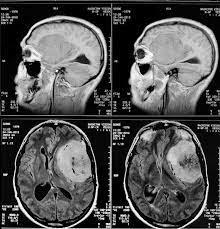

दुनिया में ब्रेन ट्यूमर से हर साल 2 लाख मौतें हो रही हैं। इस समस्या को कम करने वैज्ञानिकों ने दुनिया का पहला फिंगर-प्रिक टेस्ट विकसित किया है। वैज्ञानिकों के अनुसार, परियोजना का उद्देश्य एक सरल परीक्षण किट बनाना था, जिसका उपयोग मरीज घर पर कर सकते हैं। वैज्ञानिकों के मुताबिक, इस टेस्टिंग से गंभीर और शुरुआती ट्यूमर के बारे में पता चल जाएगा। वैज्ञानिकों के मुताबिक, अगर ब्रेन ट्यूमर शुरुआत में पता चल जाता है तो प्रारंभिक उपचार के बाद यह ठीक हो सकता है, हालांकि इसके बाद भी ट्यूमर वापस होने का अनुमान है, इसलिए आसान परीक्षण से इसके बारे में पता रखना गंभीर स्थिति में जाने से रोकने का काम करेगा।शोधकर्ताओं ने कहा कि नया परीक्षण बहुत आसान है। टेस्टिंग के दौरान बस उंगली पर अचानक चुभन होगी।

यह परीक्षण एमआरआई स्कैन की आवश्यकता को कम करेगा। यह किट मरीजों के पैसे बचाएगी, यानी कोई मरीज महंगे विकल्प की ओर नहीं जाएगा। इससे डॉक्टरों पर भी बोझ के कम होने की संभावना है। वैज्ञानिकों का मानना है कि इससे देश भर में हजारों लोगों के जीवन में सकारात्मक बदलाव आने की संभावना है।